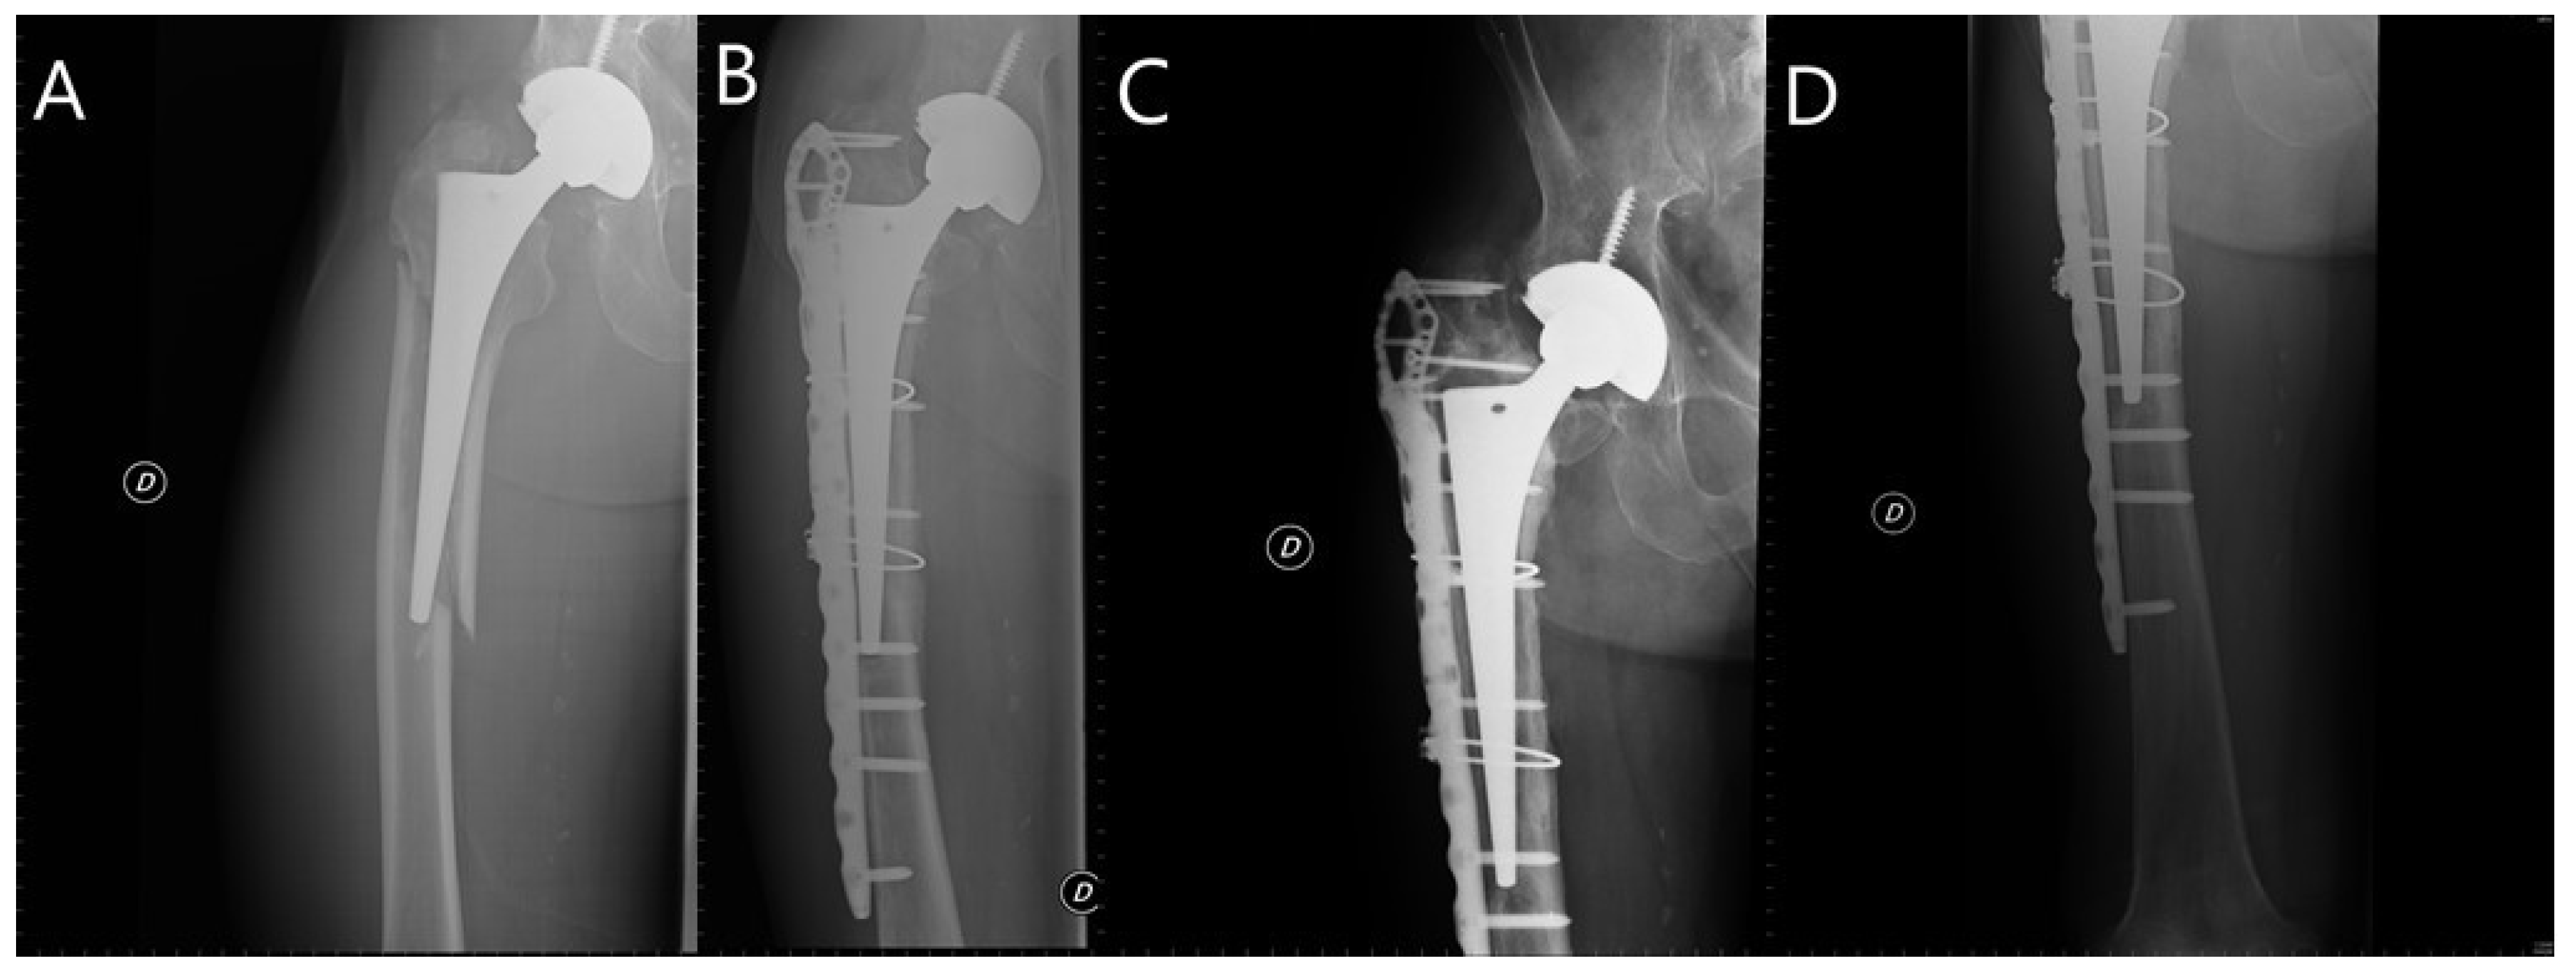

- González-Martín, D.; Pais-Brito, J.L.; González-Casamayor, S.; Guerra-Ferraz, A.; Ojeda-Jiménez, J.; Herrera-Pérez, M. New Sub-Classification of Vancouver B2 Periprosthetic Hip Fractures According to Fracture Pattern. Injury 2021. [Google Scholar] [CrossRef]